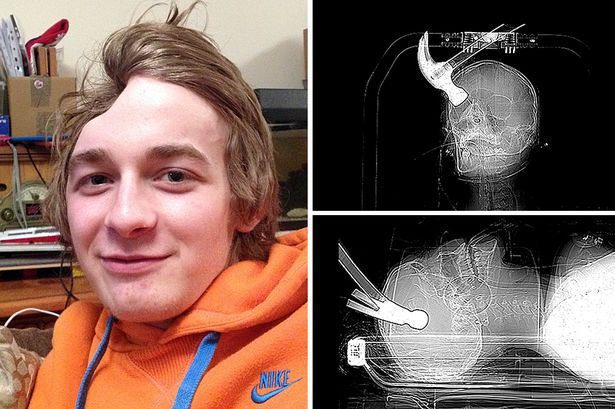

Connor Huntley foi encontrado por médicos com um martelo ainda incorporado em sua cabeça, depois de Joseph Williams, seu colega de quarto, ligar para as autoridades e confessar o terrível ataque.

A vítima teve a sorte de sobreviver ao ataque traumático, mas agora sofre de epilepsia e não é mais capaz de ser independente para realizar suas tarefas.